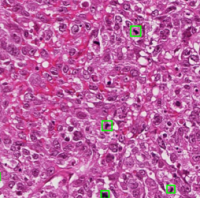

迪英加拥有世界级的尖端人工智能算法,独创的D-PathAI智能病理辅助诊断系统可对图片进行自动检测-识别-分割,高效快速处理数字病理影像。